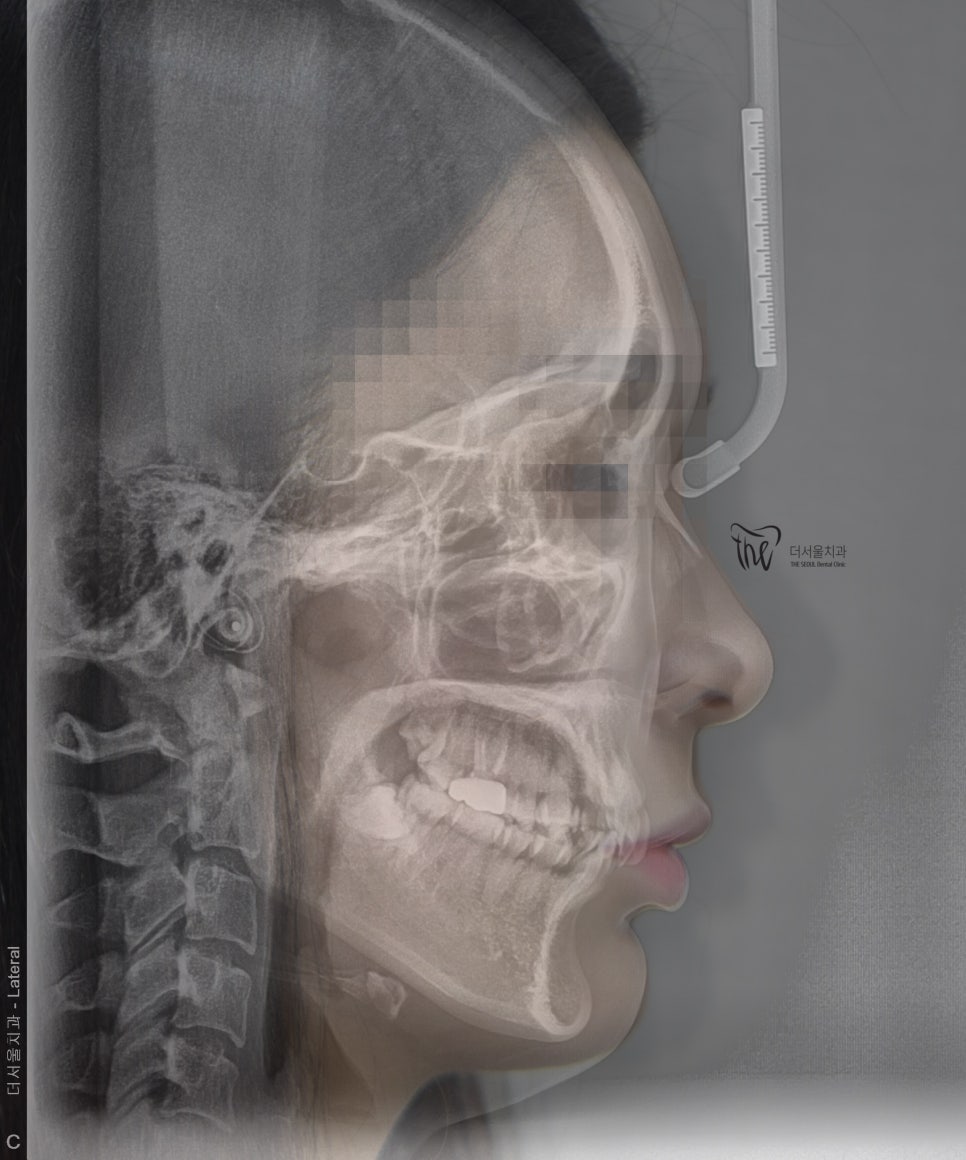

게다가, 측면 Ceph 사진을 봤을 땐

앞니가 그렇게 뻐드러져 있는 느낌은

받을 수 없습니다.